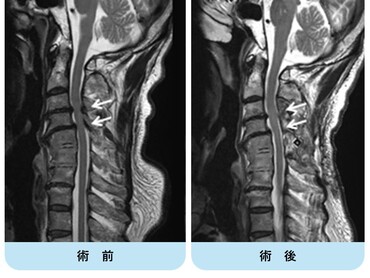

術前MRIでは多椎間で脊髄(灰色)を圧迫しています。後方手術施行後、脊髄への圧迫は改善しています。

頚椎OPLLを認め脊髄を圧迫している状態です。前方からの骨化浮上術により症状は改善しています。